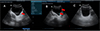

Among the 146 patients examined by ultrasound, 69 (47%) were Sh+ and 77 (53%) were Sh−. The prevalence of urinary tract disorders associated with Sh+ was significantly higher (Fisher Test; p < 0.0001) (36.23%) than in Sh− (7.80%) (Table 1). Our results show that disorders of the bladder (lower urinary tract) were much more frequent than those of the upper urinary tract. Regarding lower urinary tract disorders, bladder thickening was the most frequent (Fig. 4), which accounted for 21 patients (14.38%), followed by bladder irregularities (focal or multifocal) in 8 patients (5.48%). Severe bladder disorders such as masses and polyps were rare, with only one case observed. The prevalence of bladder wall irregularity appeared to be the same in both groups, despite the observed bladder wall thickening, which was significantly more prevalent in Sh+ cases than in Sh− (Fisher Test; p < 0.0001); the prevalence of irregularity appeared to be the same in both groups. As for upper tract disorders, they were observed in the Sh+ group only (Table 1). Dilatation of the kidneys and ureters was observed in four (2.74%) and three (2.05%) patients respectively.

![]() |

Figure 4 Ultrasound images showing some lesions observed in the bladder of patients with (Sh+) or without (Sh−) S. haematobium infection. A: Bladder of irregular shape and thickened wall (red arrow); B: Bladder of irregular shape with pseudopolyps (red arrow); C: Normal bladder; M: Male patient. |